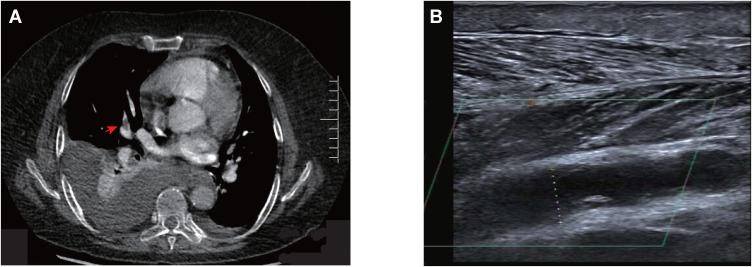

Immune checkpoint inhibitors may cause unique immune-related adverse events. Vascular thrombosis, especially arterial thrombosis, is rare but life-threatening, and little is known about its relevance to immunotherapy. Here, we reported two cases of vascular thrombosis, including venous and arterial thrombosis in cancer patients receiving anti-PD-1 antibody in combination with chemotherapy. Systemic corticosteroids and anticoagulant treatment were administered immediately in two cases. In case 1, anti-PD-1 antibody was permanently discontinued, and recurrence of vascular thrombosis was not observed during the follow-up. In case 2, the patient continued anti-PD-1 immunotherapy and unfortunately died of cerebral infarction 2 months later. This case report provides a strong evidence for the association between PD-1 blockade and vascular thrombosis and offers some general guidelines on the management of the immune-related vascular thrombosis events induced by anti-PD-1 therapy.

免疫检查点抑制剂可能会引发独特的免疫相关不良事件。血管血栓形成,尤其是动脉血栓形成,虽罕见但危及生命,而关于其与免疫治疗的相关性却知之甚少。在此,我们报告了两例血管血栓形成病例,包括接受抗PD - 1抗体联合化疗的癌症患者发生的静脉和动脉血栓形成。两例均立即给予全身性皮质类固醇和抗凝治疗。病例1中,抗PD - 1抗体被永久停用,随访期间未观察到血管血栓形成复发。病例2中,患者继续接受抗PD - 1免疫治疗,不幸的是2个月后死于脑梗死。本病例报告为PD - 1阻断与血管血栓形成之间的关联提供了有力证据,并为抗PD - 1治疗引起的免疫相关血管血栓形成事件的管理提供了一些通用指南。